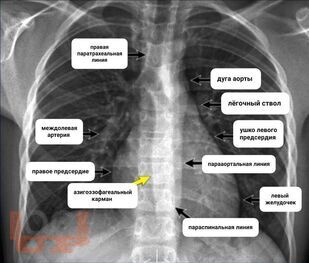

В учебном пособии представлена информация о нормальной рентгеновской анатомии органов грудной полости, вариантной анатомии, наиболее частых аномалиях развития, скиалогии, алгоритме описания рентгенограмм и основных требованиях по оформлению протокола рентгенологического исследования.